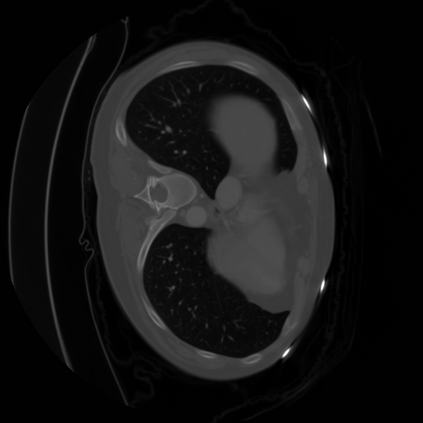

The integration of deep learning systems into healthcare has been hindered by the resource-intensive process of data annotation and the inability of these systems to generalize to different data distributions. Foundation models, which are models pre-trained on large datasets, have emerged as a solution to reduce reliance on annotated data and enhance model generalizability and robustness. DINOv2 is an open-source foundation model pre-trained with self-supervised learning on 142 million curated natural images that exhibits promising capabilities across various vision tasks. Nevertheless, a critical question remains unanswered regarding DINOv2's adaptability to radiological imaging, and whether its features are sufficiently general to benefit radiology image analysis. Therefore, this study comprehensively evaluates DINOv2 for radiology, conducting over 100 experiments across diverse modalities (X-ray, CT, and MRI). To measure the effectiveness and generalizability of DINOv2's feature representations, we analyze the model across medical image analysis tasks including disease classification and organ segmentation on both 2D and 3D images, and under different settings like kNN, few-shot learning, linear-probing, end-to-end fine-tuning, and parameter-efficient fine-tuning. Comparative analyses with established supervised, self-supervised, and weakly-supervised models reveal DINOv2's superior performance and cross-task generalizability. The findings contribute insights to potential avenues for optimizing pre-training strategies for medical imaging and enhancing the broader understanding of DINOv2's role in bridging the gap between natural and radiological image analysis. Our code is available at https://github.com/MohammedSB/DINOv2ForRadiology